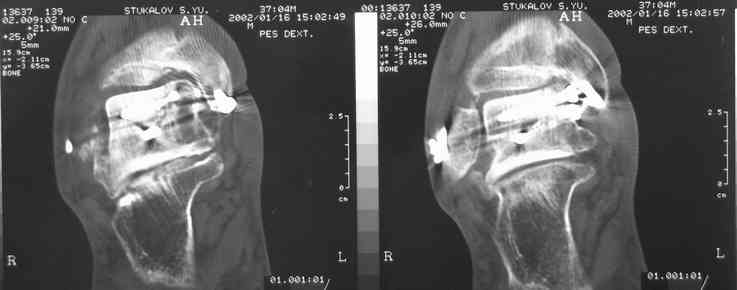

В Вашей ситуации мы произвели открытую репозицию и фиксацию металлоконструкциями. Все зажило первично, посттравматического дефартроза избежать не удалось. Пациент от артродезирующих операций в отдаленном периоде отказался.